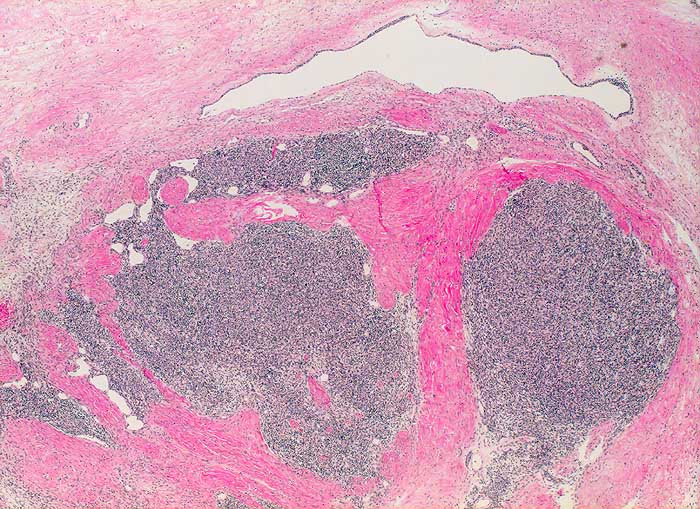

Thymom Typ A (WHO)

Lobulierter bekapselter Tumor. Fokale Zystenbildung.

Makroskopie: 8x6x6cm grosser Knoten, welcher von 3 Seiten von Serosa bedeckt ist. Auf Schnitt hellbrauner gelappter Tumor, welcher durch dicke fibröse Septen unterteilt ist. Der Tumor ist von einer Kapsel umgeben. Kein Durchbruch.

Es handelt sich hier um ein grosses gutartiges Thymom ohne maligne Zellelemente. Der Tumor in überwiegenden Anteilen mit einem medullären Phänotyp mit spindeligen Tumorzellen, entsprechend einem medullären Thymom nach der Müller-Hermelink-Klassifikation und einem Typ A-Thymom nach der WHO-Klassifikation. Der Tumor allseits umkapselt und im Gesunden entfernt ohne invasives Wachstum. Insgesamt hat das Thymom vom Typ A bei vollständiger Umkapselung und Entfernung im Gesunden eine sehr gute Langzeitprognose.